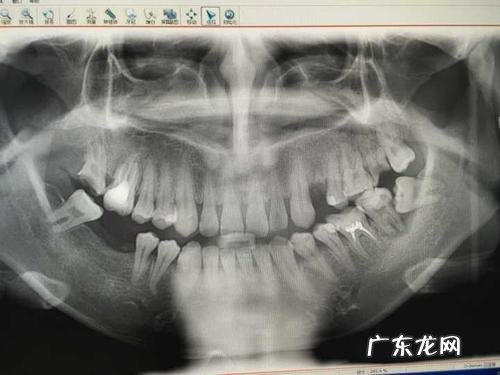

【乳牙是满口换吗 27岁满口乳牙】孩子有20颗牙, 也就是说有20颗乳牙和32颗成年牙, 但是有很多中国人最后4颗牙都长不出来 。 那四颗牙齿很多都是成年后长出的, 也叫智齿, 有些人不可能全部长出来, 所以能看到的成年人的牙齿在28颗到32颗之间, 但是如果你拍个x光片, 可以看到所有正常的成年人都有32颗牙齿 。 每个人都有32颗恒牙, 实际上有28颗牙齿在起作用 。 当一两颗牙齿脱落时, 不会影响全身健康, 但当剩下的牙齿少于20颗时, 就会影响身体很多系统的功能 。 这个时候, 如果及时修复掉的牙齿, 将20颗以上的功能性牙齿保留在口腔中, 就会减缓人的衰老速度, 有助于延长人的寿命 。 这是因为人的牙齿不到20颗, 食物不能充分咀嚼, 影响消化功能 。 发音会受到不良影响, 外观会显得老气, 对人的心理会产生负面影响 。 另外, 牙齿是人体重要的平衡器官, 很多注意力集中的身体活动和脑力劳动都需要牙齿咬合配合 。 牙齿少于20颗时, 人的平衡功能受到影响, 很容易出现活动失误和摔倒 。 目前, 中国正在倡导一种“8020运动”, 即现在就关注牙齿健康, 让你80岁还能有20颗牙齿 。 正常门牙32颗, 犬齿8颗, 前磨牙4颗, 后磨牙8颗, 后磨牙12颗 。 最后两颗后磨牙是智齿, 一般在16岁以后长出, 或者终身不长出 。